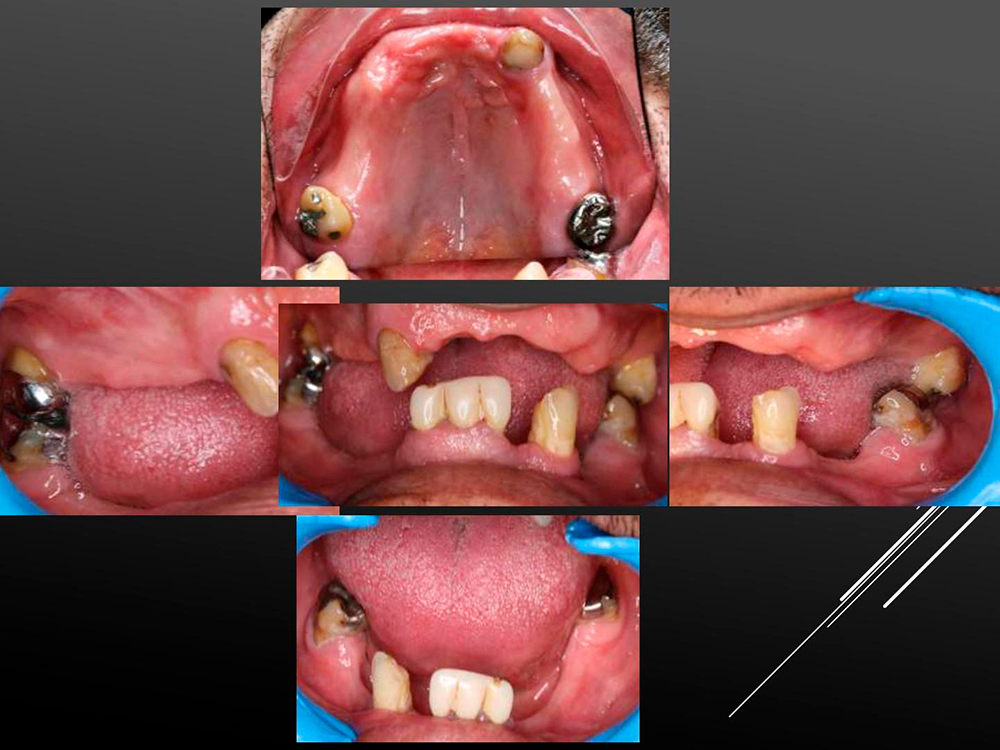

All-On-4 Mix: Entire Arch Restoration with Lock-in and Low-Lock Abutments. The wide range of DSI prosthetic parts gives the surgeon the freedom to find the ideal solution for every case. Here is a perfect example - the removable denture based on the Premium Spiral Implants with a strong Loc-in anchoring the posterior part and slim highly esthetic Low-lock abutments on the anterior zone.